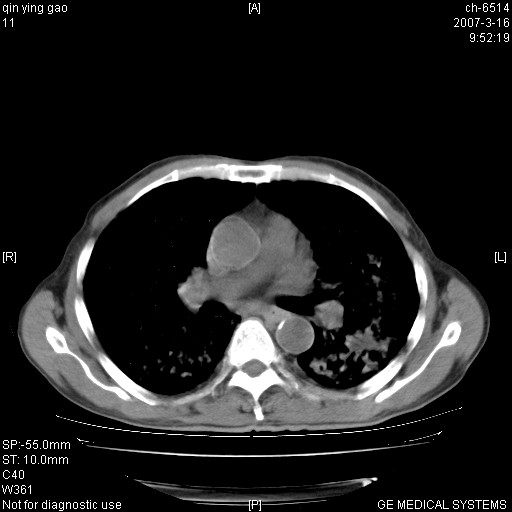

男,64岁.乏力2个月,畏寒、发热1月余。体重下降。血沉加快,白细胞不高。

双肺以中上肺野为著斑片状.结节壮密度增高影 左上肺前段可见小类圆钙化灶 纵隔淋巴结无明显肿大

双肺以中上肺野为著斑片状.结节壮密度增高影,纵隔淋巴结无明显肿大。考虑:

两肺弥漫分布的斑片状影,部分融合,左肺及纵隔淋巴结见钙化影,考虑1。tb,2。肺泡细胞癌,建议查痰检